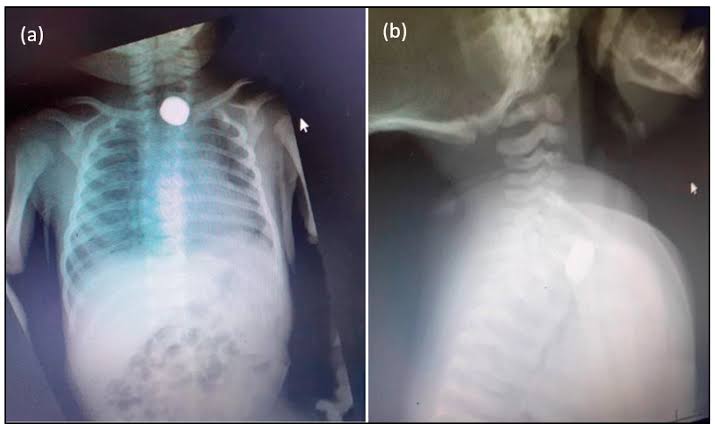

বোতাম ব্যাটারি গিলে বিপন্ন শিশুদের জীবন — সতর্ক থাকার আহ্বান চিকিৎসকদেরদেখতে ছোট্ট, ওজনেও হালকা। কিন্তু একটি বোতাম ব্যাটারি শিশুদের জন্য হয়ে উঠছে প্রাণঘাতী বিপদের কারণ। খেলনা গাড়ি, রিমোট, দেয়াল ঘড়ি, টর্চ কিংবা বিভিন্ন ইলেকট্রনিক ডিভাইসে ব্যবহৃত এই ব্যাটারি শিশুদের হাতে প্রায়শই চলে আসে। কৌতূহলবশত খেলতে খেলতেই অনেক ছোট শিশু এগুলো মুখে দিয়ে ফেলে—আর তখনই শুরু হয় ভয়াবহ বিপদের সম্ভাবনা।

চিকিৎসক বিশেষজ্ঞদের মতে, বোতাম ব্যাটারি যদি শ্বাসনালিতে আটকে যায়, শিশুর শ্বাস বন্ধ হয়ে মুহূর্তের মধ্যেই মৃত্যুও হতে পারে। আর যদি খাদ্যনালিতে ঢুকে যায়, ব্যাটারির ভেতরের রাসায়নিক পদার্থ খাদ্যনালির আস্তরণ পুড়িয়ে দেয়, রক্তক্ষরণ এমনকি ছিদ্রও করতে পারে। শরীরের ভেতরে ব্যাটারি যত বেশি সময় থাকে, ক্ষতি তত মারাত্মক হয়ে ওঠে।